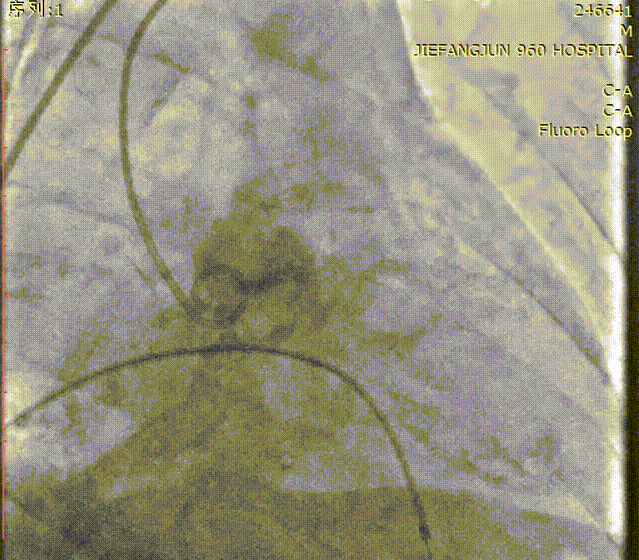

导丝成功跨瓣后,送入18mm Prizballoon®球囊成功通过主动脉瓣狭窄处,在180 bpm快速起搏下行球囊预扩张。

导丝跨瓣

球囊预扩